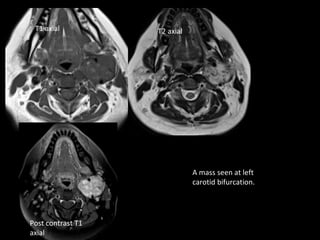

Case 2

• Slow growing neck mass on left side.

T1 axial          T2 axial

A mass seen at left

carotid bifurcation.

Post contrast T1

axial

Angiogram showing Tumor at

carotid bifurcation displacing

internal and external carotid

arteries

Salt and pepper sign

Diagnosis- carotid body tumor

• Characteristically is a hypervascular tumor

located at carotid bifurcation.

• It is a paraganglioma or chemodectoma.